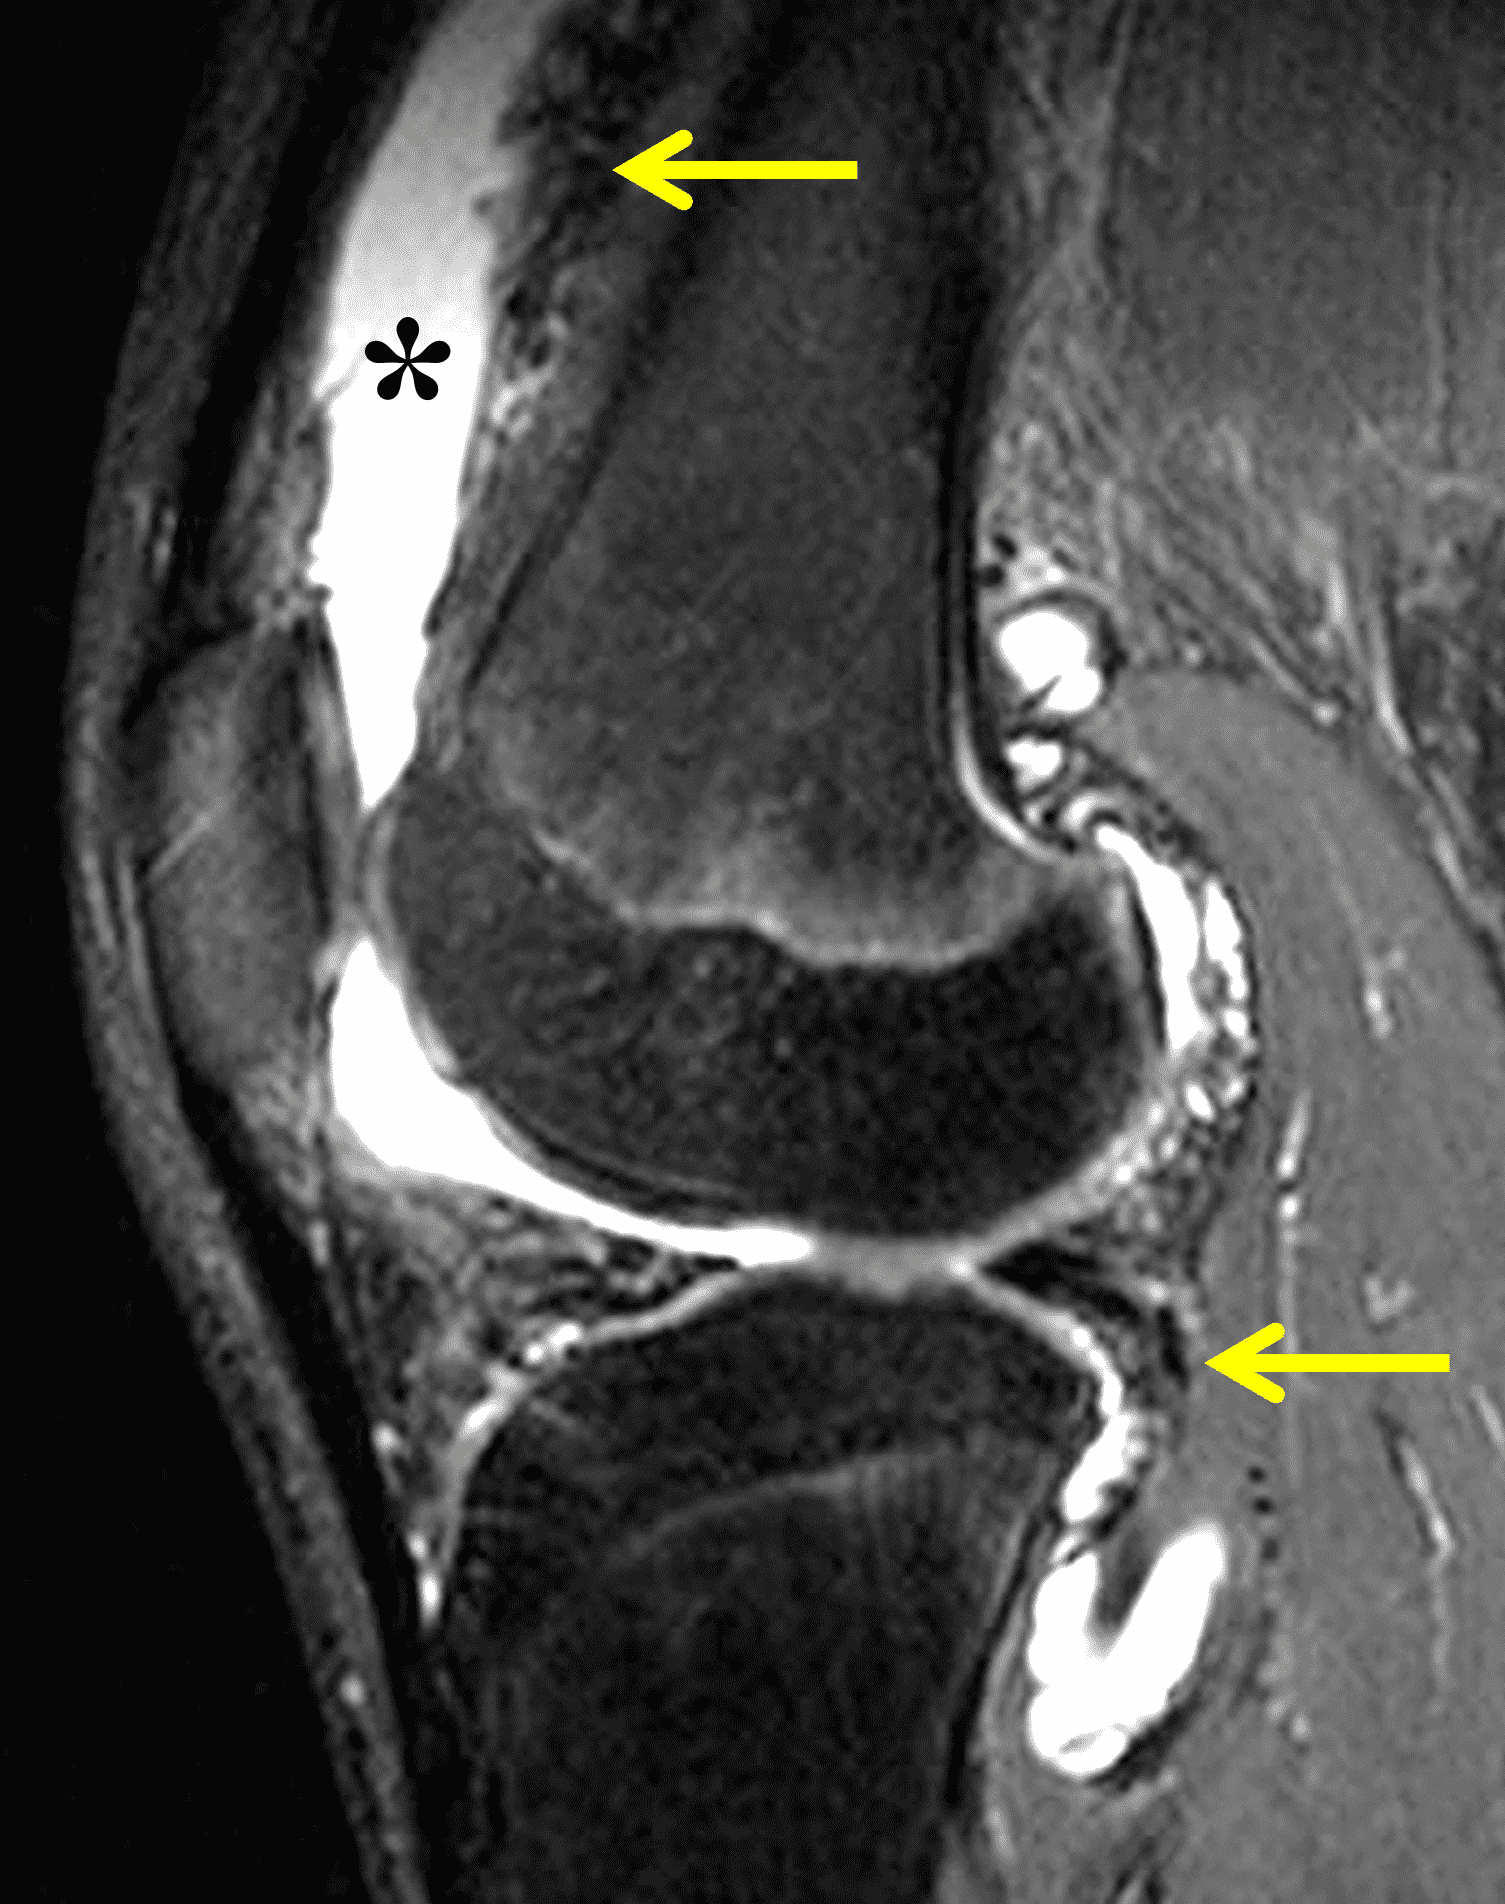

Figure 2: (2A) The coronal image shows a large effusion and severe hypertrophic synovitis (asterisks) in the knee. (2B) On the sagittal image the hypertrophic synovium (asterisks) involves the suprapatellar and infrapatellar recesses as well as the anterior and posterior intercondylar notch. A reactive lymph node (arrow) is present in the popliteal fossa. (2C) The axial image demonstrates myositis (arrows) involving the popliteus and peroneus longus muscles. Note the preserved articular cartilage, lack of erosions, and the absence of subcutaneous or marrow edema.

The causative spirochete invades the synovium, triggering a host inflammatory response that leads to synovial hypertrophy and inflammation, resulting in the characteristic clinical symptoms and imaging findings associated with Lyme arthritis.2 Common MR findings associated with Lyme arthritis include synovitis, joint effusion, popliteal lymphadenopathy, and myositis predominantly involving the popliteus (Figure 4).2,3,9 In contrast to acute septic arthritis due to more common bacteria, subcutaneous edema, marrow edema, erosions, and osteomyelitis are uncommon (Figure 4C).

Figure 4: Lyme arthritis. Fat-suppressed, fluid-sensitive images. (4A) Transverse image shows severe proliferative synovitis in the anterior and posterior joint recesses (arrows). Note the lack of surrounding subcutaneous edema. (4B) In addition to synovitis, the sagittal image shows multiple reactive lymph nodes (red arrows) and popliteal myositis (white arrow). (4C) Coronal image also shows patchy non-joint centered marrow edema in the distal femur and proximal tibia (asterisks), which is uncommon in Lyme disease compared to acute septic arthritis.